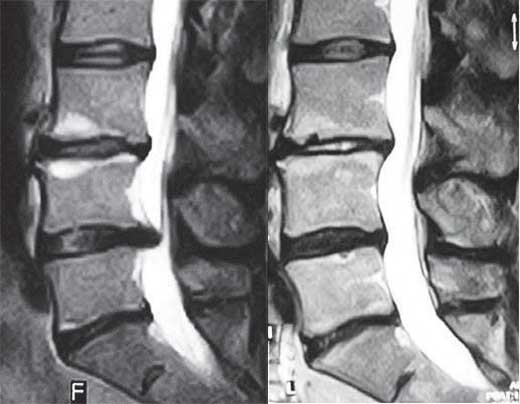

МРТ пациентов прошедших в нашей клинике несколько курсов УБР

Иллюстрация 1

На левом снимке поясничный отдел позвоночника после операции в сегментах LIII–LIV и LV–SI. Рецидив грыжи межпозвонкового диска в сегменте LIV–LV.

На правом снимке состояние поясничного отдела позвоночника после 6 курсов УБР.